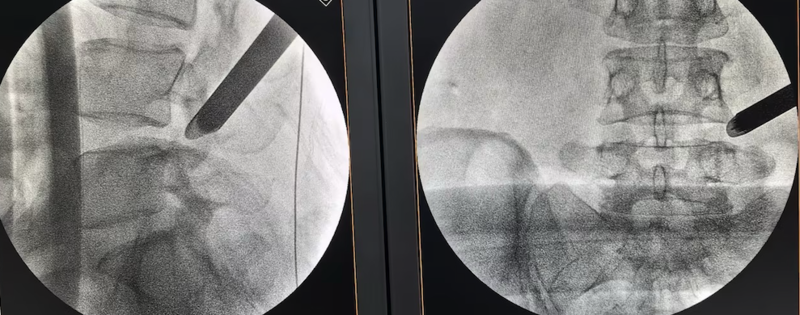

△微创椎间孔镜技术

菏泽高三学生安安(化名)的故事同样令人动容。他于备考关键期出现腰腿疼痛麻木,无法久坐,当地医院诊断为腰椎间盘突出症,建议手术。“孩子高考时间紧张,为了寻求更信任的专家手术,我们来到了青岛。”安安家长说,通过校友介绍,他们找到了曾为校友亲戚成功手术的李强主任。

“我们采用椎间孔镜技术,创口只有7毫米。”李强主任团队通过铅笔粗细的通道,完成了神经减压和髓核摘除。术后当天,安安的疼痛麻木感就消失了。出院时他说:“感谢医院,我终于能安心冲刺高考了。”